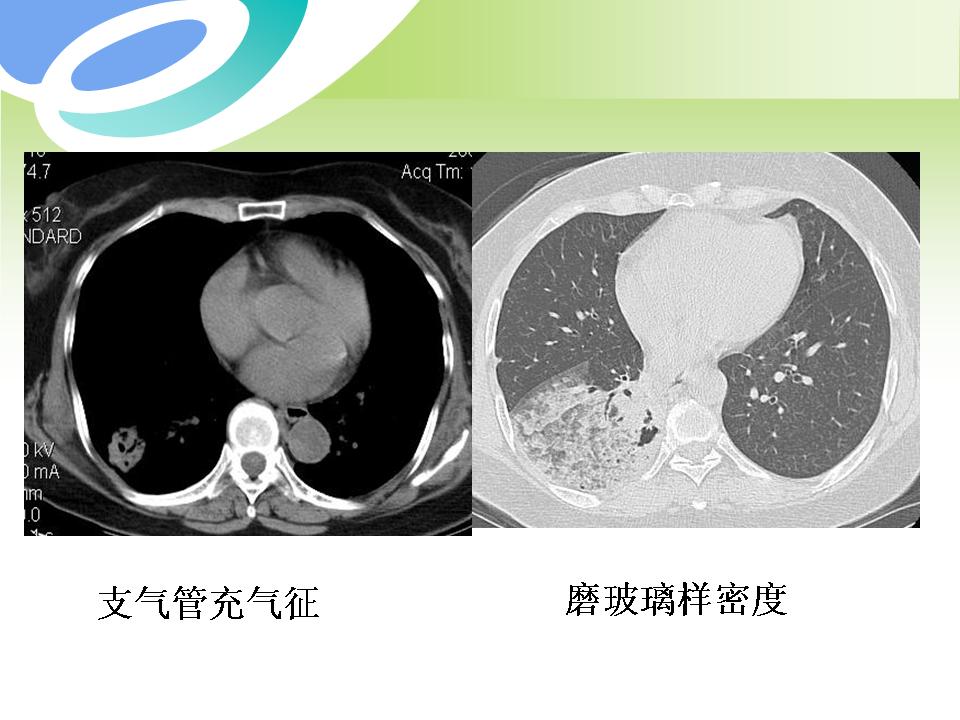

肺部病变的CT基本征象